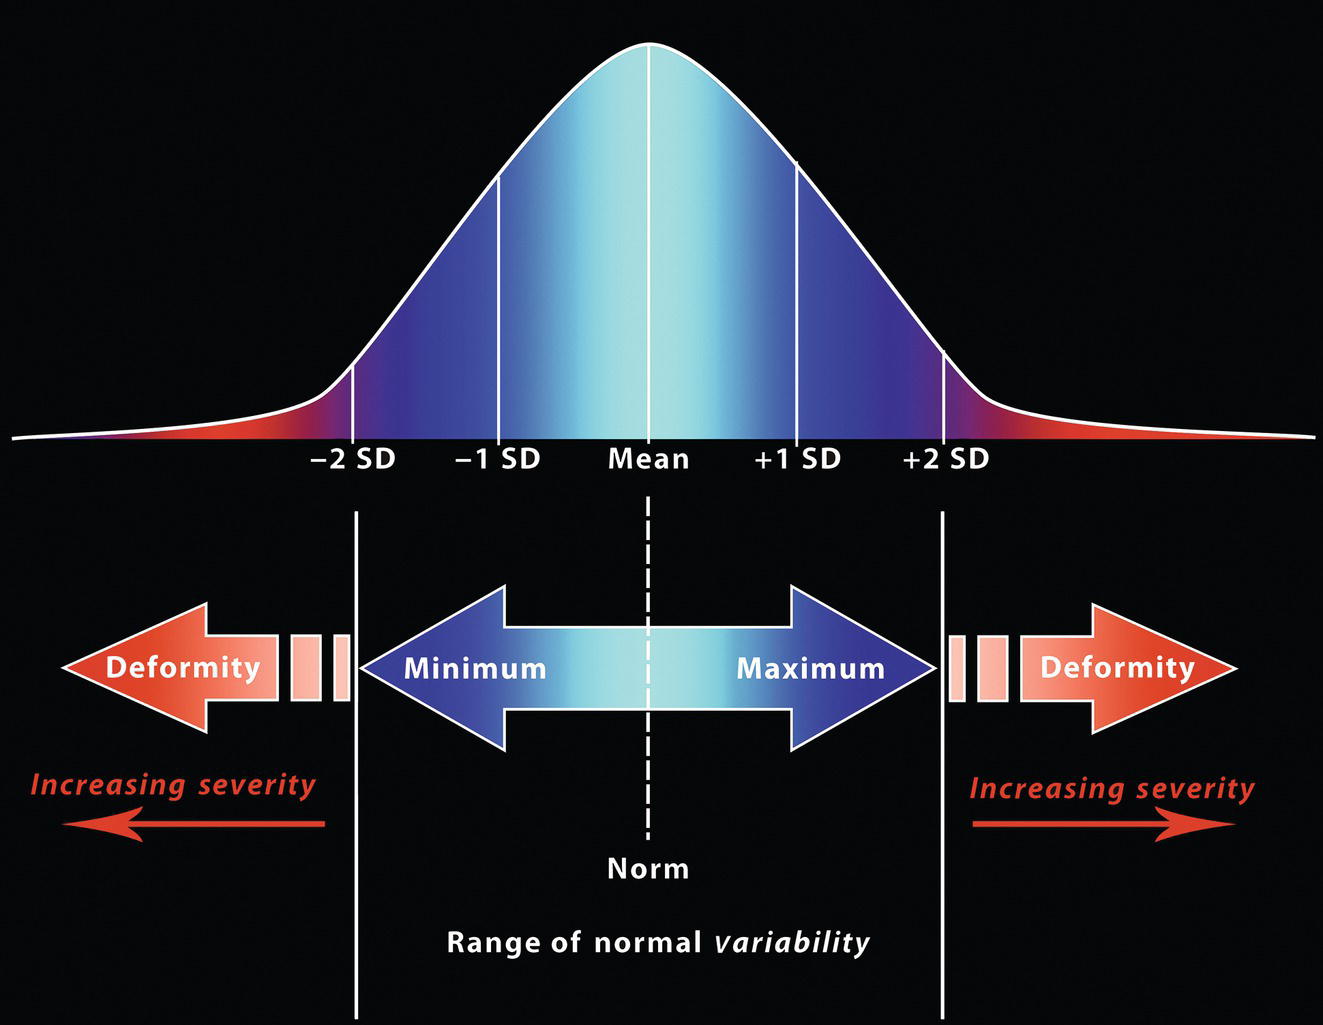

‘It is the common wonder of all men, how among so many millions of faces, there should be none alike’. Sir Thomas Browne (1605–82), English physician and writer, Religio Medici (1643)1 Individual variability is a fundamental principle in human biology. One of the most variable and distinguishable parts of the human body is the craniofacial complex. Clinicians will often compare a patient’s craniofacial measurements and proportions to the so‐called population norms (normative values) or even to classical ideals. However, Simon (1926) stated: ‘all we ever find are variations; an exact, ideal normal does not exist, cannot exist. And this is our enigma; in theory we will never find the normal, in practice we forever feel its need and apply it constantly’.2 The use of population norms may be logically enhanced by evaluating normal ranges of variability. Therefore, clinicians must have a thorough understanding of the normal ranges of variability in every aspect of craniofacial form, depending on age, sex and ethnic variability. Developmental disorders, as well as traumatic injuries and pathological conditions, may lead to deformities of the head and the face. Therefore, clinicians need to have a thorough understanding of the normal anatomy and morphological range of variation of the craniofacial complex in both males and females of different ages and ethnic groups, to act as guidelines when treatment planning the restoration of normal craniofacial proportions. Classifications that are useful for descriptive purposes include: A proportion index provides a numerical expression of the proportionality of a region of the craniofacial complex. The use of proportion indices dates back through the history of craniometry, particularly in the late nineteenth century. Linear (chord) or surface (arc) distances of the skull were measured between a variety of defined craniofacial landmarks; with any two measurements, the smaller was expressed as a percentage of the larger in order to provide a proportion index value. These could be used to provide an indication of skull shape. Figure 8.1 Determination of the normality or abnormality of any craniofacial measurement (or proportion index value) obtained from patients may be evaluated by comparison with the normative values obtained from a normal (average representative) population sample. The normal range of measurements is provided by the mean ±2 standard deviations (SD). The shape of the normal distribution curve shown is determined by the population standard deviation. Craniofacial parameters with small SDs have narrow, taller curves and those with large SDs have broader, flatter curves. Approximately 68% of all values fall within the range of ±1 SD from the mean and 95% within the range of ±2 SD from the mean. The normal range of variability for any craniofacial parameter is taken as being equal to the mean ±2 SDs. Greater differences may be perceived as deformities of gradually increasing severity. The leading researcher in the field of craniofacial anthropometry from the mid‐1960s to the early 2000s was Leslie Farkas, from the University of Toronto. Farkas et al. collected a large quantity of highly relevant anthropometric data between 1968 and 1984, from 2564 individuals.3 These data were used to provide 166 individual facial ratios, presented as proportion indices. In the creation of an index, the smaller measurement is multiplied by 100 (numerator) and divided by the larger measurement (denominator). Thus, a proportion index involves two linear craniofacial anthropometric measurements, with the smaller being expressed as a percentage of the larger. Proportion indices permit objective, quantitative assessment of facial morphology and proportions. Farkas3 identified two basic categories of proportion indices: Each proportion index will have a mean index value and a range of variation for a given population group, based on age, sex and ethnicity. The standard deviation (SD) determines the normal (average) range of variability of an index, from 2 SD below to 2 SD above the mean. Index values within this normal range are regarded as variations of normal proportions.4 Measurements within ±1 SD of the mean are regarded as optimal. The relationship between two measurements is disproportionate if the proportion index value is outside the normal range (Figure 8.1).4 For a number of facial parameters, single morphological measurements or proportion index values may have a large SD and, therefore, wide normal ranges of variation; as such, only measurements or proportion index values which differ considerably from the mean of the population will be perceived as deformities. Conversely, other facial parameters may have very small normal ranges of variability, in which case even a small difference from the mean may be perceived as a deformity. The cephalic index (index cephalicus) is a numerical expression of the ratio between the head width (biparietal diameter) and head length (fronto‐occipital diameter) of a living person. The cephalic index (CI) is calculated by the formula (Figure 8.2): Figure 8.2 Cephalic index. Where: The cephalic index is used in anthropometry to classify head types as (Table 8.1; Figure 8.3): Table 8.1 Classification of anatomical head types Index values according to Martin and Saller.5 Figure 8.3 Head types. The highest cephalic index values occur in the Chinese and the lowest values in African Americans. The larger index values of the Chinese differ significantly from those of whites or blacks (Table 8.2).6 A comparison of the cephalic index values of three ethnic groups was undertaken; North American Caucasians, northern European (German) and eastern European (Czech). The index values indicated a mesocephalic head type for both sexes of North American Caucasians and northern Europeans; and a brachycephalic (short‐wide) head type for the eastern Europeans.6 The head circumference is measured in the horizontal plane around the head, through the glabella and opisthocranion. However, it may be measured across ophyron (the point ‘On’, in the mid‐sagittal plane, of a line tangent to the upper limits of the eyebrows) rather than glabella in order to eliminate the effect of development of the frontal sinuses and superior orbital rims on head circumference.5,7 African Americans have the largest and the Chinese have the smallest head circumference for both sexes. The head circumference is slightly larger for blacks than for whites for both sexes.6 The initial step in facial analysis involves the examination of the face in frontal view in order to assess the overall facial shape. The variety of facial shapes is almost limitless. However, a simple assessment will allow an overall categorization of the basic facial shape. The basic facial shape in frontal view may be any combination of the following: Table 8.2 Cephalic index of three ethnic groups Data modified from Farkas.6 SD = standard deviation. Table 8.3 Head circumference of three ethnic groups Data modified from Farkas.6 SD, standard deviation. Figure 8.4 Facial height‐to‐width ratios. Variations in facial height and width result in an innumerable variety of the three basic facial shapes (round, square and triangular). For example, an oval facial type is a combination of an overall round face combined with increased vertical facial height and/or reduced facial width. The relationship of vertical facial height to facial width is an important indicator of overall facial shape. There are three methods of evaluating the vertical facial height‐to‐width proportion. These may be presented as proportions, percentages or indices: The facial index (index facialis or index of the morphological face height) is a numerical expression of the ratio between the facial height (nasion to menton) and the bizygomatic facial width (zygion to zygion) of a living person. The facial index (FI) is calculated by the formula: Where: The facial index is used in anthropometry to classify faces as (Table 8.4; Figure 8.6): Figure 8.5 Facial types according to Albrecht Dürer. (Modified from Dürer, 15288.) Figure 8.6 Facial types. Table 8.4 Classification of anatomical face types Index values: male according to Garson, 1885;9 and female according to Martin and Saller, 1957.5 The term facial divergence was introduced by the orthodontist‐anthropologist Milo Hellman,10 although the concept had been described by Albrecht Dürer (1528) (Figure 8.7).8 It is essentially a description of the slope or inclination of the face in the sagittal plane (Figure 8.8). It is determined by the sagittal position of soft tissue pogonion (Pog’) and subnasale (Sn) relative to a vertical line dropped from glabella (G’), with the subject’s head in natural head position. The factor that discriminates and distinguishes facial divergence from profile convexity or concavity is the sagittal position of subnasale (Sn) relative to the G’‐Pog’ line. In order for the face to diverge anteriorly or posteriorly, yet not to exhibit signs of convexity or concavity, subnasale (Sn) must be on or nearly on the G’‐Pog’ line; i.e. the upper facial plane (UFP, G′‐Sn) and the lower facial plane (LFP, Sn‐Pog’) are in a straight line, but diverge anteriorly or posteriorly. Figure 8.7 Facial divergence according to Albrecht Dürer. (Modified from Dürer, 15288.) Figure 8.8 Facial divergence. Anthropometric data from North American Caucasian males and females with untreated Class I dental occlusions describing normal facial divergence and ranges of variability has been provided.11 Mean values of facial divergence are negative, with the faces being slightly posteriorly divergent. Anterior divergence does not occur until two standard deviations from the mean. Facial divergence is essentially an ethnic variation in facial profile form. With a straight profile, i.e. no excessive profile convexity or concavity, anterior or posterior facial divergence is compatible with a normal maxillo‐mandibular and dental occlusal relationship. Figure 8.9 Facial profile contour according to Albrecht Dürer. (Modified from Dürer, 15288.) Figure 8.10 Facial profile contours. The contour of the facial profile may be described as convex, straight or concave. This concept was described by Albrecht Dürer (1528) (Figure 8.9).8 With the patient in NHP, the overall contour of the facial profile may be described by the relationship between two lines: the upper facial plane (UFP), connecting glabella (G’) to subnasale (Sn), and the lower facial plane (LFP), connecting subnasale to soft tissue pogonion (Pog’). In a straight profile, these two lines form a nearly straight line. Such a facial profile is termed orthognathic (Greek orthos: correct or straight; gnathos: jaw). An angle between these two lines indicates facial profile convexity (pogonion behind relative to subnasale in the sagittal plane), or facial profile concavity (pogonion ahead relative to subnasale in the sagittal plane). A convex profile indicates a skeletal Class II jaw relationship (and/or sagittal chin deficiency), and a concave profile indicates a skeletal Class III jaw relationship (and/or sagittal chin excess). However, profile convexity or concavity does not of itself indicate whether the maxilla or mandible/chin is at fault (Figure 8.10). Legan and Burstone12 described the angle of facial convexity for the soft tissue profile. It is formed by the two intersecting lines, the UFP (G′‐Sn) and the LFP (Sn‐Pog′). The mean value is estimated to be 12° ± 4°. An increase in the angle in a clockwise direction is positive; anticlockwise is negative. A high positive value suggests facial profile convexity and a Class II skeletal jaw relationship; a smaller positive value, or a negative value, suggests facial profile concavity and a Class III skeletal jaw relationship. However, the value of this angle does not reveal whether the maxilla or mandible/chin is responsible for the sagittal jaw discrepancy. Figure 8.11 Angle of facial profile convexity (facial contour angle). Downs13 described the angle of convexity, formed by the intersection of line nasion to point A (NA) and line point A to pogonion (A‐Pog). Superior extension of the A‐Pog line forms an angle with the NA line; if behind the NA line, the angle is read as positive, indicating a Class II (convex) skeletal profile. A negative angle of convexity indicates a Class III (concave) skeletal profile. Downs provided a range of values from −8.5° to 10°, with a mean of 0°. Again, as with the facial contour angle, the angle of convexity does not determine the localization of the deformity to the maxilla or mandible/chin. An investigation was carried out with the objective of assessing how lower facial profile convexity influences perceived attractiveness. The lower facial profile of an idealized image was altered incrementally between 14° and −16°, creating a range of images which were evaluated by pretreatment orthognathic surgery patients, laypeople and clinicians. A straight profile was perceived as most attractive and greater degrees of convexity or concavity deemed progressively less attractive, but a range of 10° to −12° was deemed acceptable; beyond these values surgical correction was desired. Patients were most critical, and clinicians were more critical than laypeople.14 The facial angle indicates the relative sagittal prominence of soft tissue pogonion. It is formed by the intersection of the true horizontal plane (or Frankfort Horizontal plane) with a facial vertical plane (N′‐Pog’). The angle should be approximately 90°–92°. A greater angle indicates prominence of soft tissue pogonion; an angle less than 90° indicates retrusion of soft tissue pogonion. The soft tissue facial angle does not of itself determine the aetiology of the sagittal position of soft tissue pogonion, which may be due to one or a combination of: Consequently, the facial angle must be used in conjunction with other measurements and analyses. In addition, when constructing the facial vertical line (N’‐Pog’), if the sagittal position of nasion is not acceptable, it may be adjusted to a more ideal position. The alternative is to use soft tissue glabella (G’) rather than nasion. Downs13 described the facial angle as the inferior inside angle in which the facial line (N‐Pog) intersects the Frankfort Horizontal plane. Downs found a mean value of 88° with a range of 82°–95°. It indicates the relative sagittal position of the mandible/chin to the upper face. Figure 8.12 Facial angle. FH, Frankfort Horizontal plane; TrH, true horizontal plane. Figure 8.13 The relationship of the cranial base angle (saddle angle) and anterior cranial base length on the jaw relationship. The relationship of the anterior to the posterior cranial base is of particular importance in the diagnosis of facial profile contour. This relationship depends on the extent of growth at the sphenoethmoidal and spheno‐occipital synchondroses. The cranial base angle (or saddle angle) represents the orientation of the anterior cranial base (SN line) relative to the posterior cranial base (S‐Ba line).15 The average adult values (bearing in mind that there is negligible change in this angle after the age of six years) for the angle N‐S‐Ba are16: As such, the cranial base angle is an important determinant of craniofacial form, as it influences the sagittal position of the face relative to the neurocranium and the sagittal prominence of the mandible relative to the maxilla. A significantly increased cranial base angle contributes to a skeletal Class II jaw relationship, whereas a reduced cranial base angle contributes to a skeletal Class III jaw relationship. If basion is difficult to identify on a lateral cephalometric radiograph, articulare may be used instead, i.e. the posterior cranial base is drawn between sella and articulare. The average adult values for the angle N‐S‐Ar are16: The anterior cranial base length, measured from sella to nasion, may also influence the jaw relationship. For example, increased anterior cranial base length may lead to a Class II jaw relationship, with the maxilla ahead of the mandible in the sagittal plane, whereas reduced cranial base length may lead to a Class III jaw relationship, with the maxilla behind the mandible in the sagittal plane. The average adult values for the anterior cranial base length are16: Figure 8.14 Parasagittal profile contour. An additional and extremely important consideration is the description of the parasagittal profile (Figure 8.14). It is necessary to evaluate the sagittal relationships of the soft tissues from the infraorbital area to the paranasal area to the parasymphyseal area. For example, maxillary hypoplasia may lead to lack of bony support and flattening in the infraorbital region and paranasal hollowing; with a normal parasymphyseal area, this will lead to the appearance of a concave parasagittal profile. The directional pattern of facial growth has a significant effect on facial profile form. Deviations from the normal pattern of jaw growth may be in a predominantly vertical or horizontal direction. Alternative terms are hyperdivergent facial growth pattern (referring to the excessive divergence of the maxillary, occlusal and mandibular planes in relation to each other and to the anterior cranial base).17 Such a pattern of growth leads to a hyperdivergent facial type, alternatively termed a high angle patient (referring to the increased mandibular plane angle), long face deformity or long face syndrome.18 If the hyperdivergent growth is the primary aetiology to an anterior open bite, the terms skeletal open bite or apertognathia (Latin apertus: open; Greek gnathos: jaw) may be used.19,20 The maxilla rotates downward and backward (posterior vertical maxillary excess), as does the mandible during growth. This leads to reduced sagittal projection of the chin. Such a vertical facial growth pattern will tend to be associated with a posterior pattern of mandibular growth rotation. Figure 8.15 Hyperdivergent, ‘high angle’ facial type.